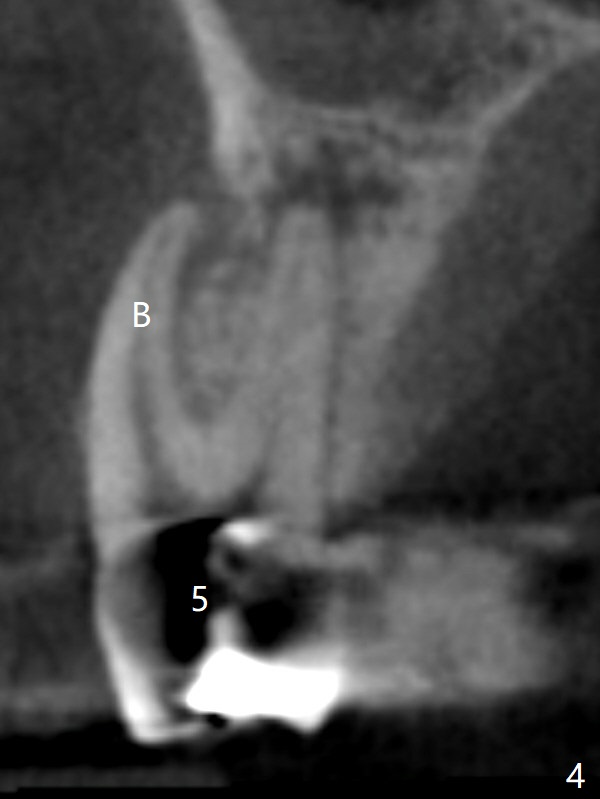

A 64-year-old man requests implant restoration after the upper FPD dislodges (Fig.1). The measurement of the septal height at #2 by PA (Fig.2) is not as precise as CBCT (Fig.11, taken 4 years earlier). There appears to be 2.8 mm bone apical to the tooth #4 (Fig.2); in contrast, the bone is more or less buccal and palatal to the root apex shown by CT (Fig.5). Furthermore CT more clearly shows apical lesions of the tooth #5 (Fig.3,4) than PA (Fig.2). In addition to pulpal test, RCT should be done for #5 prior to implant placement at #4.